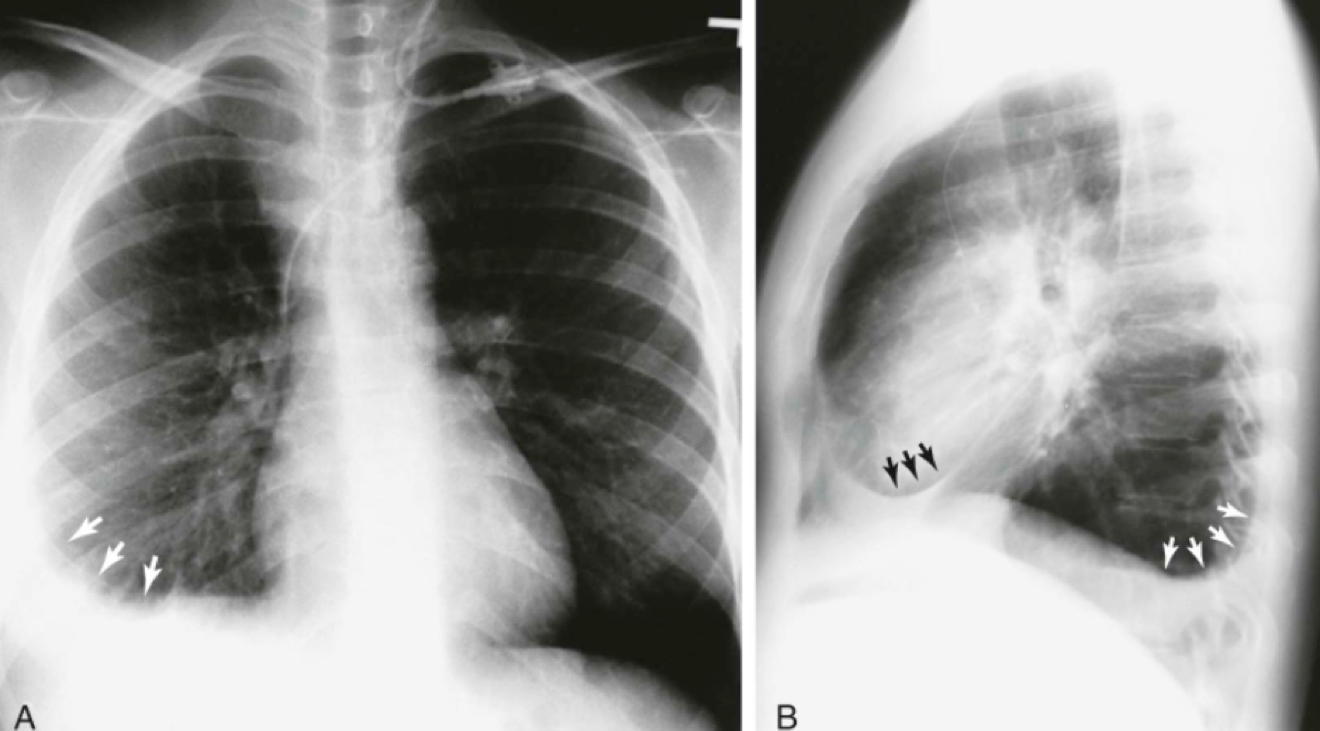

Question 22

Question

In "Kerley B Lines" , fluid may be seen in the interlobular septa at the basal aspects of the lung. Where is it always located and the position of it?

Answer

• inside the lungs; horizontal

• inside the lungs; vertical

• inside the ribs; horizontal

• inside the ribs; vertical

Question 23

In what diseases will you see this?

• COPD

• CHF

• Tuberculosis

• Pneumothorax